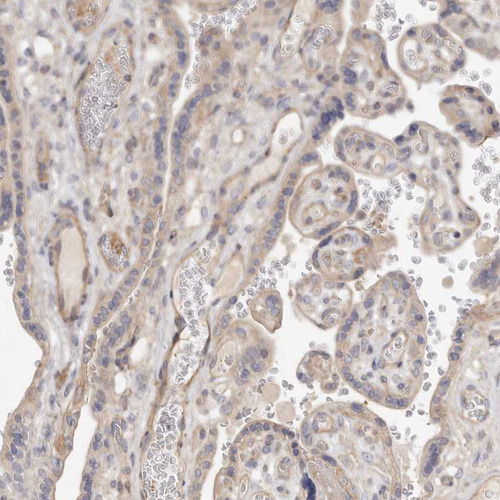

Immunohistochemical staining of human placenta shows moderate cytoplasmic positivity in trophoblastic cells.